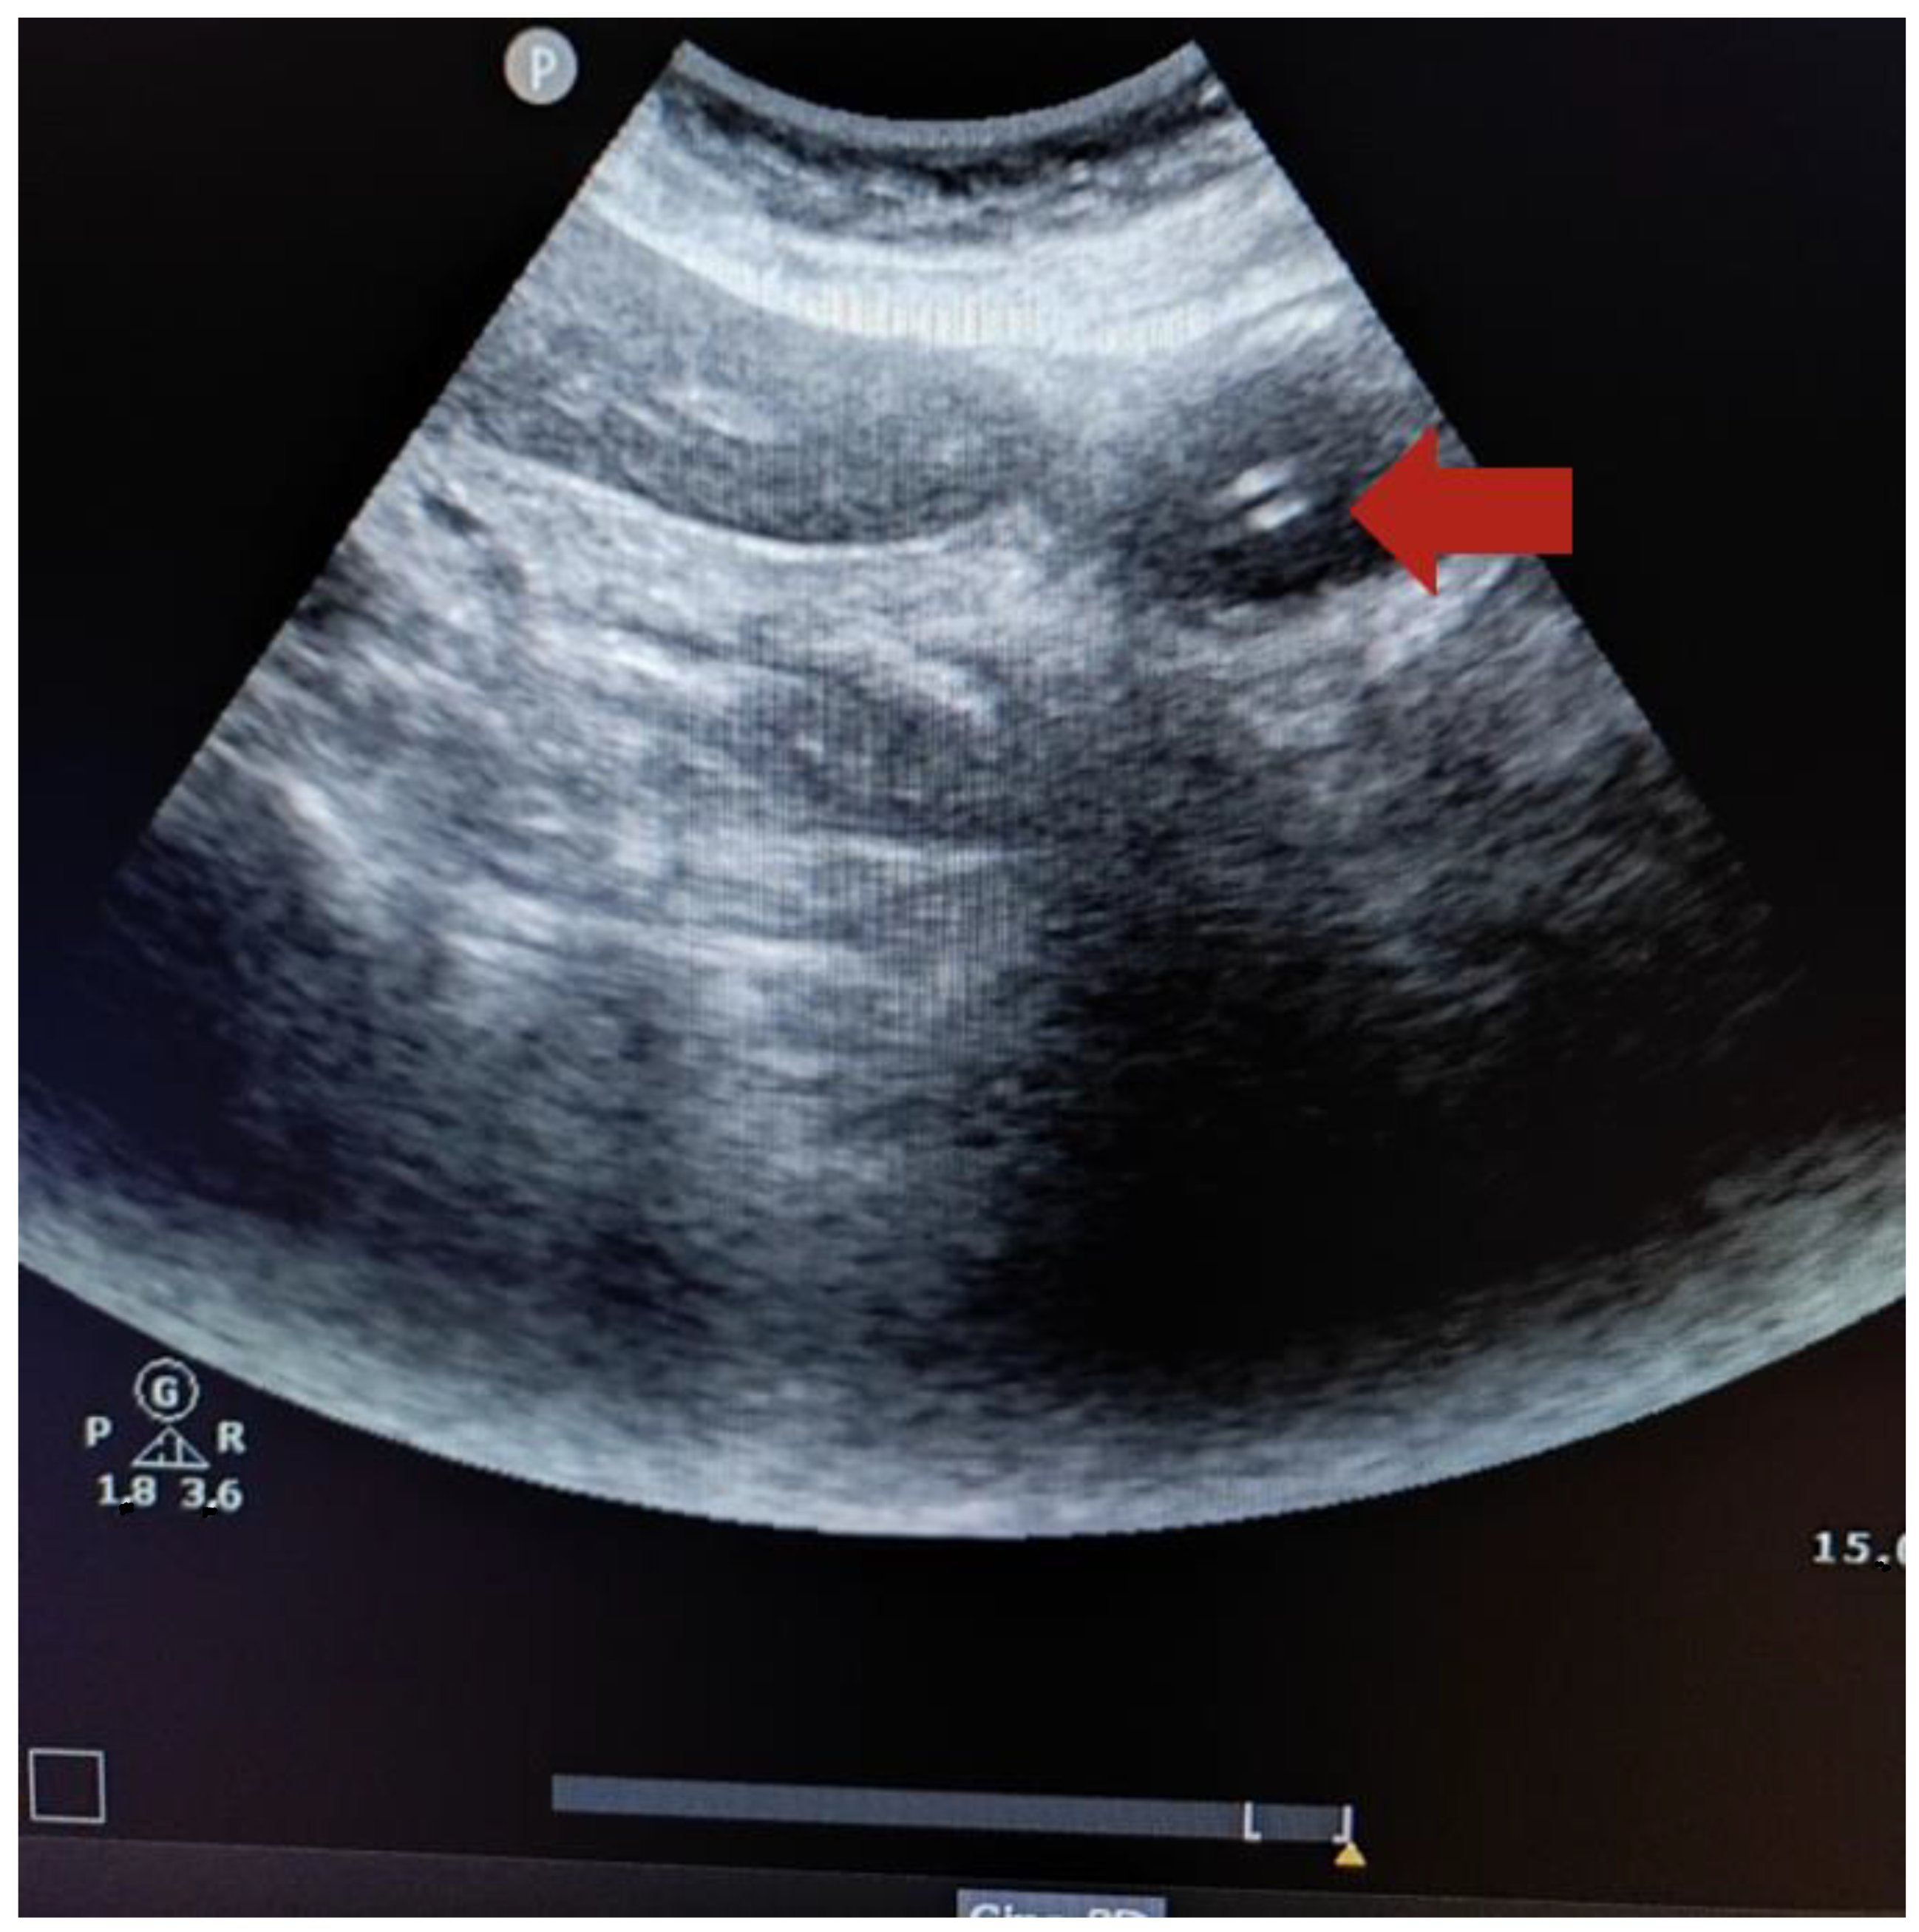

2.6. Technique to Perform the Ultrasound

- Zatelli, M.; Vezzali, N. 4-Point ultrasonography to confirm the correct position of the nasogastric tube in 114 critically ill patients. J. Ultrasound 2017, 20, 53–58. [Google Scholar] [CrossRef] [PubMed]

- Brun, P.; Chenaitia, H.; Lablanche, C.; Pradel, A. 2-Point Ultrasonography to confirm correct position of the gastric tube in prehospital setting. Mil. Med. 2014, 179, 959–963. [Google Scholar] [CrossRef]